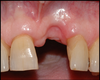

Gencive très inflammatoire

Déchaussement = migration des gencives